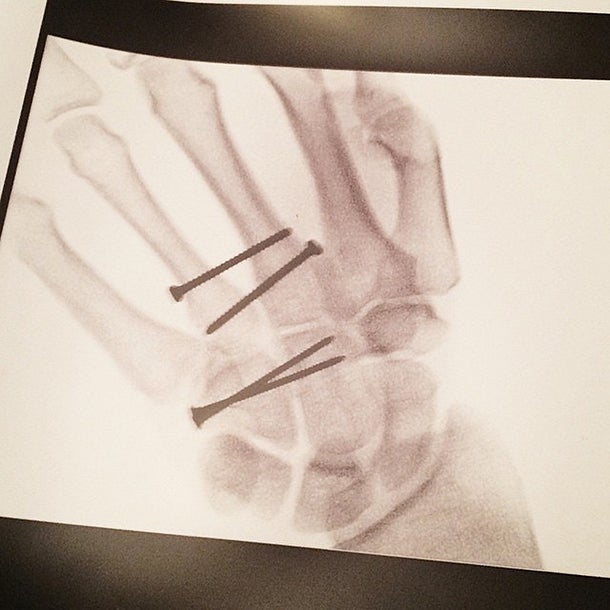

Ligetys trockener Kommentar auf Facebook: „Habe versucht, meine Hand in zwei Teile zu zerlegen.“ Und weiter: „Ich will mir nicht vorstellen, was für ein Brei meine Hand ohne meine Handschuhe mit den Protektoren jetzt wäre.“ Als Draufgabe postete er ein Bild von seiner verschraubten Hand.

© Facebook/Privat